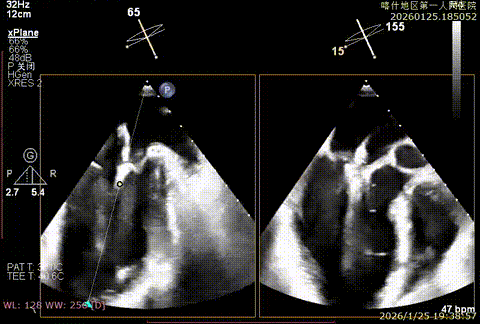

该例患者为DMR,脱垂区域较宽,术前制定手术策略:使用2把XTR先于患者外侧交界至1区部位进行钳夹。术中房间隔穿刺高度为4.0cm。成功穿刺后将SGC和XTR-CDS依次送入左心房,通过操控“M”旋钮调节SGC,使二尖瓣夹避开华法林脊,成功定位于2区正上方。在2区进行弹道测试成功后,进行Orientation调整。第一把于外侧交界区夹持,第二把于1区夹持,术中成功捕捞和夹持瓣叶后缓慢关紧夹臂,TEE检查见二尖瓣反流程度降低至1+,术后平均跨瓣压差3mmHg,手术顺利结束。

重度反流

3D enface进行Orientation调整

捕捞并夹持瓣叶

反流降低

第二枚XTR定位

Orientation调整

捕捞并夹持瓣叶,反流有效降低

组织桥稳定

术后平均跨瓣压差3mmHg